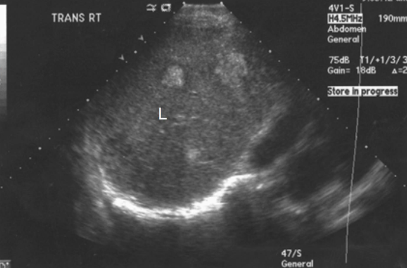

What is the echogenicity of the mass in the liver?

Hypoechoic